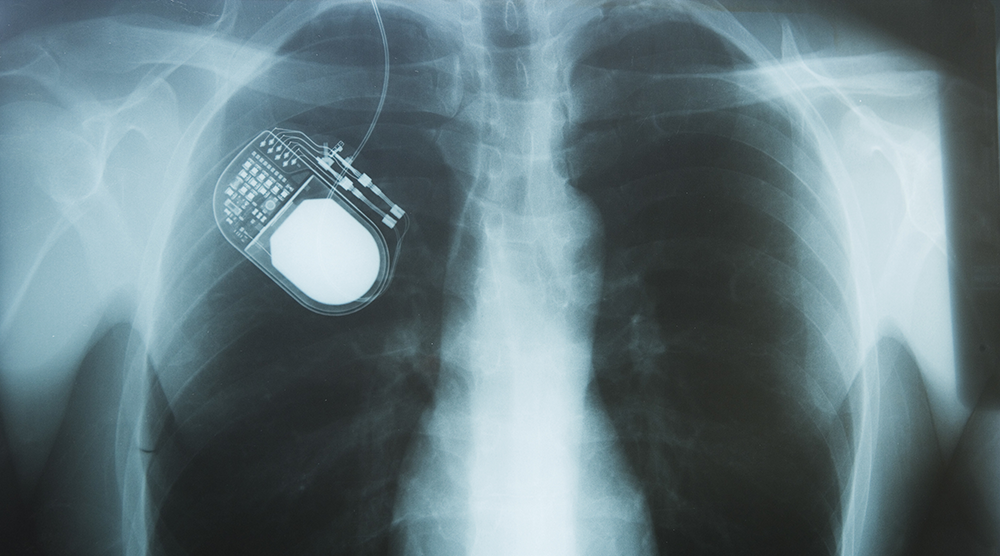

Elektrika v telesu

Najbolj znana elektronska naprava, ki jo vsajamo v naše telo, je srčni spodbujevalnik. Šved Arne Larsson je prvi človek na svetu, ki so mu leta 1958 v telo vsadili srčni spodbujevalnik. Delal je le nekaj ur, zato so ga nadomestili z drugim, ki je delal le nekaj dni. Arneju Larssonu so zamenjali kar 22 različnih srčnih spodbujevalnikov.

A danes srčni spodbujevalnik ni edini vsadek, ki lahko izboljša življenje ljudem. Kar 30 jih imamo v Sloveniji, ki se jih vsadi v telo za zdravljenje različnih bolezenskih stanj, kot so na primer sladkorna bolezen (inzulinska črpalka), nevrostimulator (okvara možganov ali živčnega sistema – Parkinsonova bolezen, kronična bolečina, poškodba hrbtenjače …), inkontinenca (sakralni nevromodulator) epilepsija (vagusni stimulator), ciroza jeter (alfa črpalka), okvara sluha (kohlearni implant – polžkov vsadek) idr.